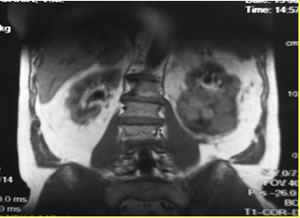

МРТ

забрюшинного пространства